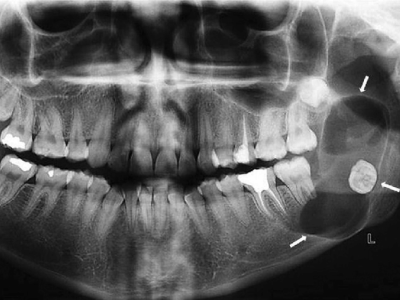

Distraction osteogenesis procedure in Hyderabad for bone lengthening

Distraction Osteogenesis

Distraction Osteogenesis is an established scientific method of elongating or increasing bone length or producing new bone without using any bone grafts, for correcting various facial deformities.